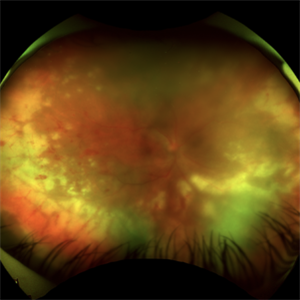

Suprachoroidal Hemorrhage

Suprachoroidal Hemorrhage

Aug 4 2025 by Anjana Mirajkar, MS Ophthalmology

A fundus photograph of a 56 year old female with a 360 degree suprachoroidal hemorrhage with a 360 degree crumpled retina during cataract surgery.

Photographer: Dr. Anjana Mirajkar- HV Desai eye hospital ,Pune

Imaging device: optos

Condition/keywords: giant retinal tear, suprachoroidal hemorrhage